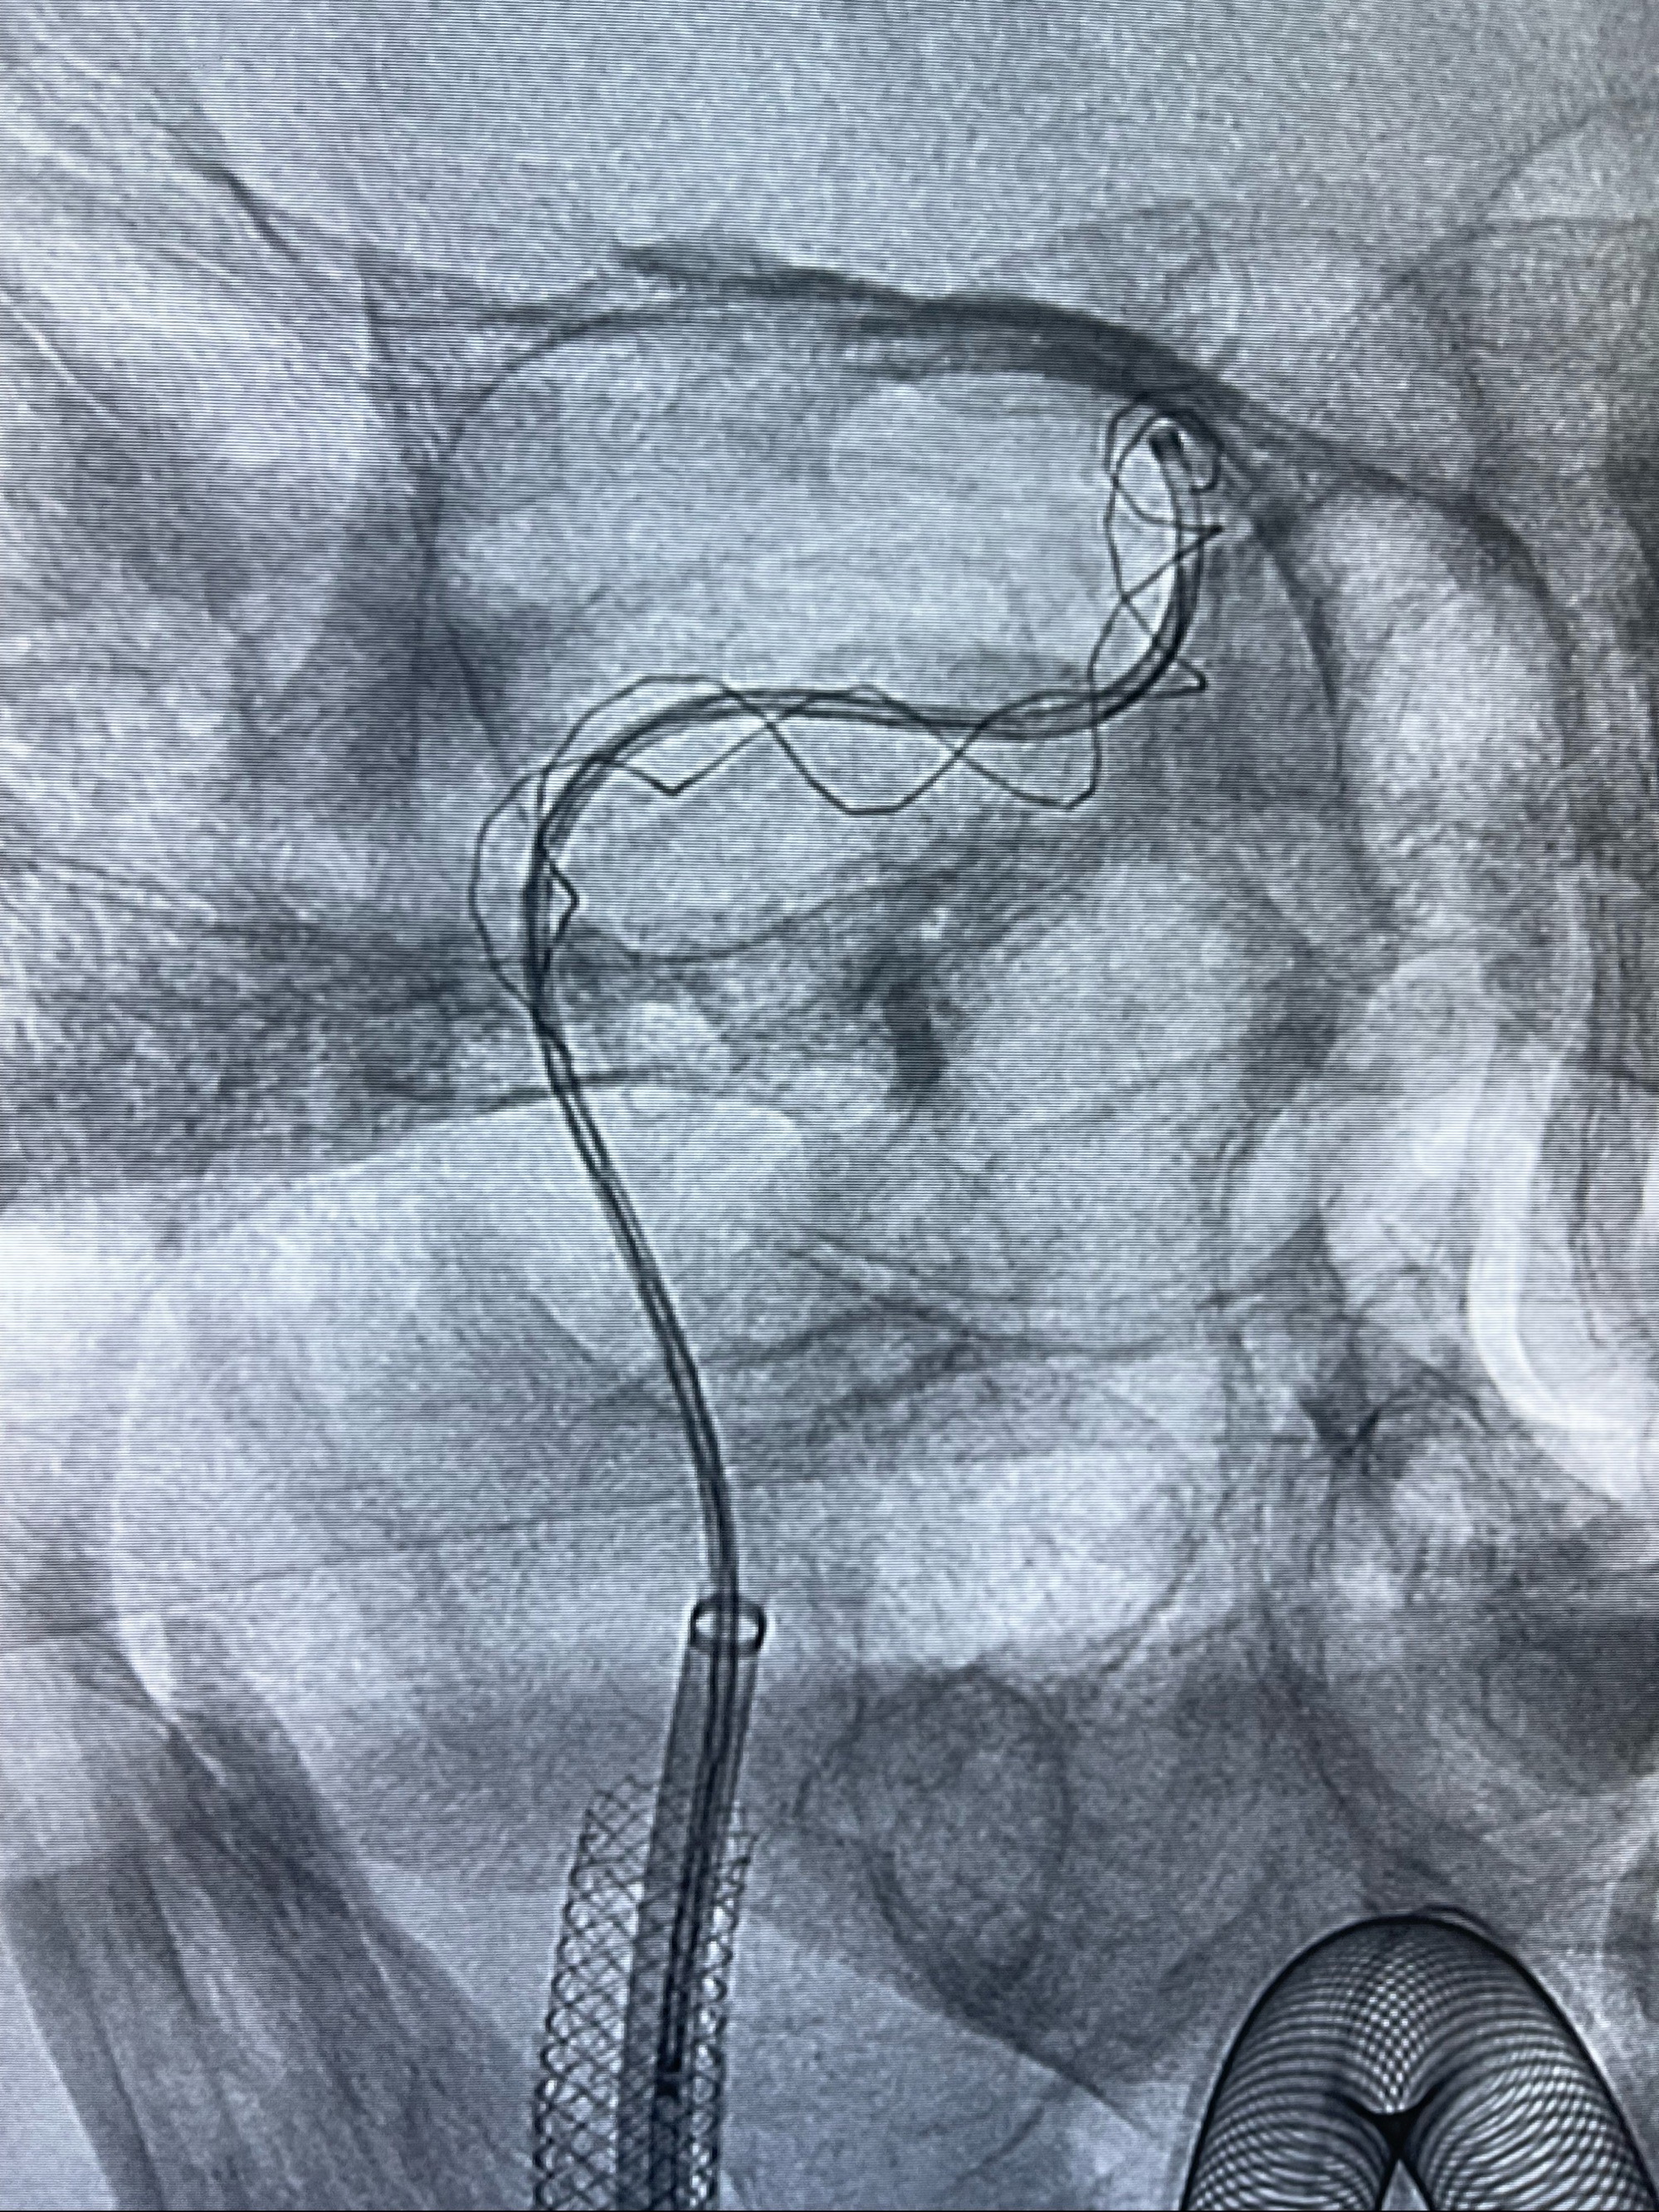

重新行“路径图”,支架导管在微导丝引导下超选择性插入至右侧颈内动脉眼段,4.5-50mmLeo支架释放,远心端位于海绵窦段,近心端位于岩骨段狭窄段以近

即刻造影显示支架贴壁佳

路径图下,5.5-50mmLeo支架导管在微导丝引导下超选择性插入远段Leo支架内

两枚支架部分重叠

多次确认支架位置及打开贴壁情况

支架完全打开,近心端位于原颈动脉支架远心端内